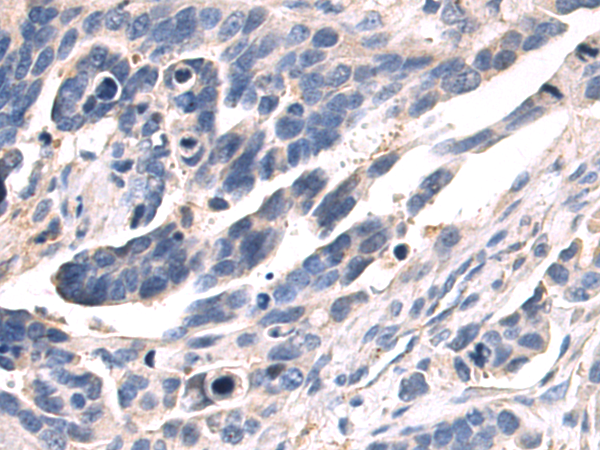

分类: 科研抗体货号: P13814别名: PLCE; PPLC; NPHS3应用: IHC反应种属: Human